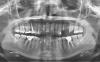

Ashley Опубликовано 21 июня, 2010 Автор Поделиться Опубликовано 21 июня, 2010 (изменено) Здравствуйте! Я сделала на днях панорамный снимок - посмотрите, пожалуйста, состояние этого зуба - 5 зуб справа. Зуб по-прежнему беспокоит, почти постоянно - боль при надкусывании и после, чувство распирания и иногда колющая боль. Может быть, этот снимок что-то прояснит. Изменено 21 июня, 2010 пользователем Ashley Ссылка на комментарий

x3m Опубликовано 21 июня, 2010 Поделиться Опубликовано 21 июня, 2010 ...Зуб по-прежнему беспокоит, почти постоянно - боль при надкусывании и после, чувство распирания и иногда колющая боль. Может быть, этот снимок что-то прояснит.эхехе...не прошло и полгода... а до восьми лет еще ой, как далеко...Ashley, все было проЯснено ДО этого снимка.Лечение тоже УЖЕ было рекомендовано выше. Даже план составлен Что Вы еще хотите услышать? Ссылка на комментарий

Ashley Опубликовано 21 июня, 2010 Автор Поделиться Опубликовано 21 июня, 2010 Хотелось бы услышать только одно - не видно ли на этом новом снимке причины боли, нет ли каких-то изменений? Только это. Ссылка на комментарий

x3m Опубликовано 21 июня, 2010 Поделиться Опубликовано 21 июня, 2010 Хотелось бы услышать только одно - не видно ли на этом новом снимке причины боли, нет ли каких-то изменений? Только это.для диагностики локальных процессов надо делать прицельные снимки (локальные, только этого зуба) - они более информативные.Но и на этом снимке есть причина - присмотритесь, в кости около верхушки корня 5 зуба затемнение. Видите? В стопиццотый раз Вам повторю - перелечивайте этот зуб. И не только этот Ссылка на комментарий

Ashley Опубликовано 21 июня, 2010 Автор Поделиться Опубликовано 21 июня, 2010 В ближайшее время перелечиваю 26 зуб, идет под коронку. Планирую имплантацию. Скажите, пожалуйста, какие еще зубы нужно перелечить? Буду Вам очень благодарна за консультацию! Ссылка на комментарий

x3m Опубликовано 21 июня, 2010 Поделиться Опубликовано 21 июня, 2010 ...18, 16, 15, 24(?), 26, 27(?), 37(?), 36, 45, 46 Ссылка на комментарий

Ashley Опубликовано 21 июня, 2010 Автор Поделиться Опубликовано 21 июня, 2010 (изменено) Скажите, а почему нужно лечить 18, 16 и 45? Что с ними? Сейчас решается судьба 24 зуба - как Вы думаете, можно ли его сохранить (восстановить) или имплантация? Изменено 21 июня, 2010 пользователем Ashley Ссылка на комментарий

x3m Опубликовано 21 июня, 2010 Поделиться Опубликовано 21 июня, 2010 Скажите, а почему нужно лечить 18, 16 и 45? Что с ними? я отметил на обзорном снимке места, где (по моему скромному мнению) необходимо работать. Некоторые из зубов (которые с вопросами) нужно увидеть в дополнительных ракурсах - осмотр, прицельный снимок...18 - большая пломба + вопрос в ее прилегании.16 - кариес.45 - тоже. пысы +фото прикуса бы приложить. Поищите правила создания тем пациентами.http://s49.radikal.ru/i125/1006/83/e6622c1af15f.jpg Сейчас решается судьба 24 зуба - можно ли его сохранить или имплантация? Как Вы думаете?думать не могу, т.к. обзора недостаточно. В идеале - макрофото+прицельный снимок 24. Ссылка на комментарий